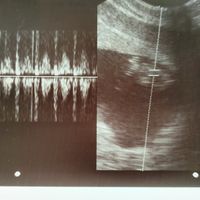

Buenos días chic@s, justo hoy hace 1 año que mi marido y yo estamos intentando ser papás sin éxito hasta ahora.. Tengo 27 años y mi marido 29. Sobre los 8 meses de búsqueda, nos hicieron las pruebas...